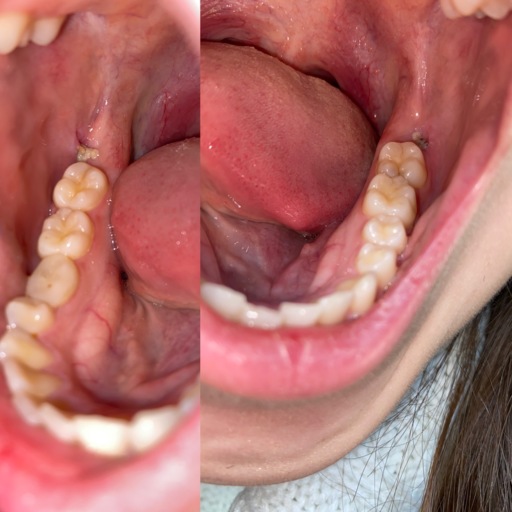

Jaw Bone Showing After Wisdom Tooth Extraction

Hello! One week ago I have two wisdom teeth removed, both being on the same side of my mouth. I had an infection on my bottom wisdom tooth and was given antibiotics prior to the extraction. Since the surgery, I have had dull pain from that one...